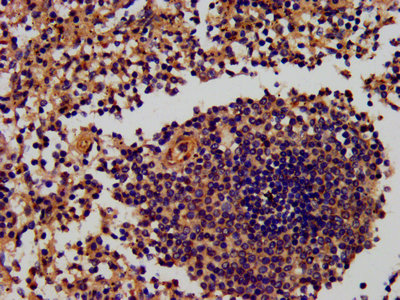

IHC image of CSB-PA019897DA01HU diluted at 1:600 and staining in paraffin-embedded human spleen tissue performed on a Leica BondTM system. After dewaxing and hydration, antigen retrieval was mediated by high pressure in a citrate buffer (pH 6.0). Section was blocked with 10% normal goat serum 30min at RT. Then primary antibody (1% BSA) was incubated at 4°C overnight. The primary is detected by a biotinylated secondary antibody and visualized using an HRP conjugated SP system.